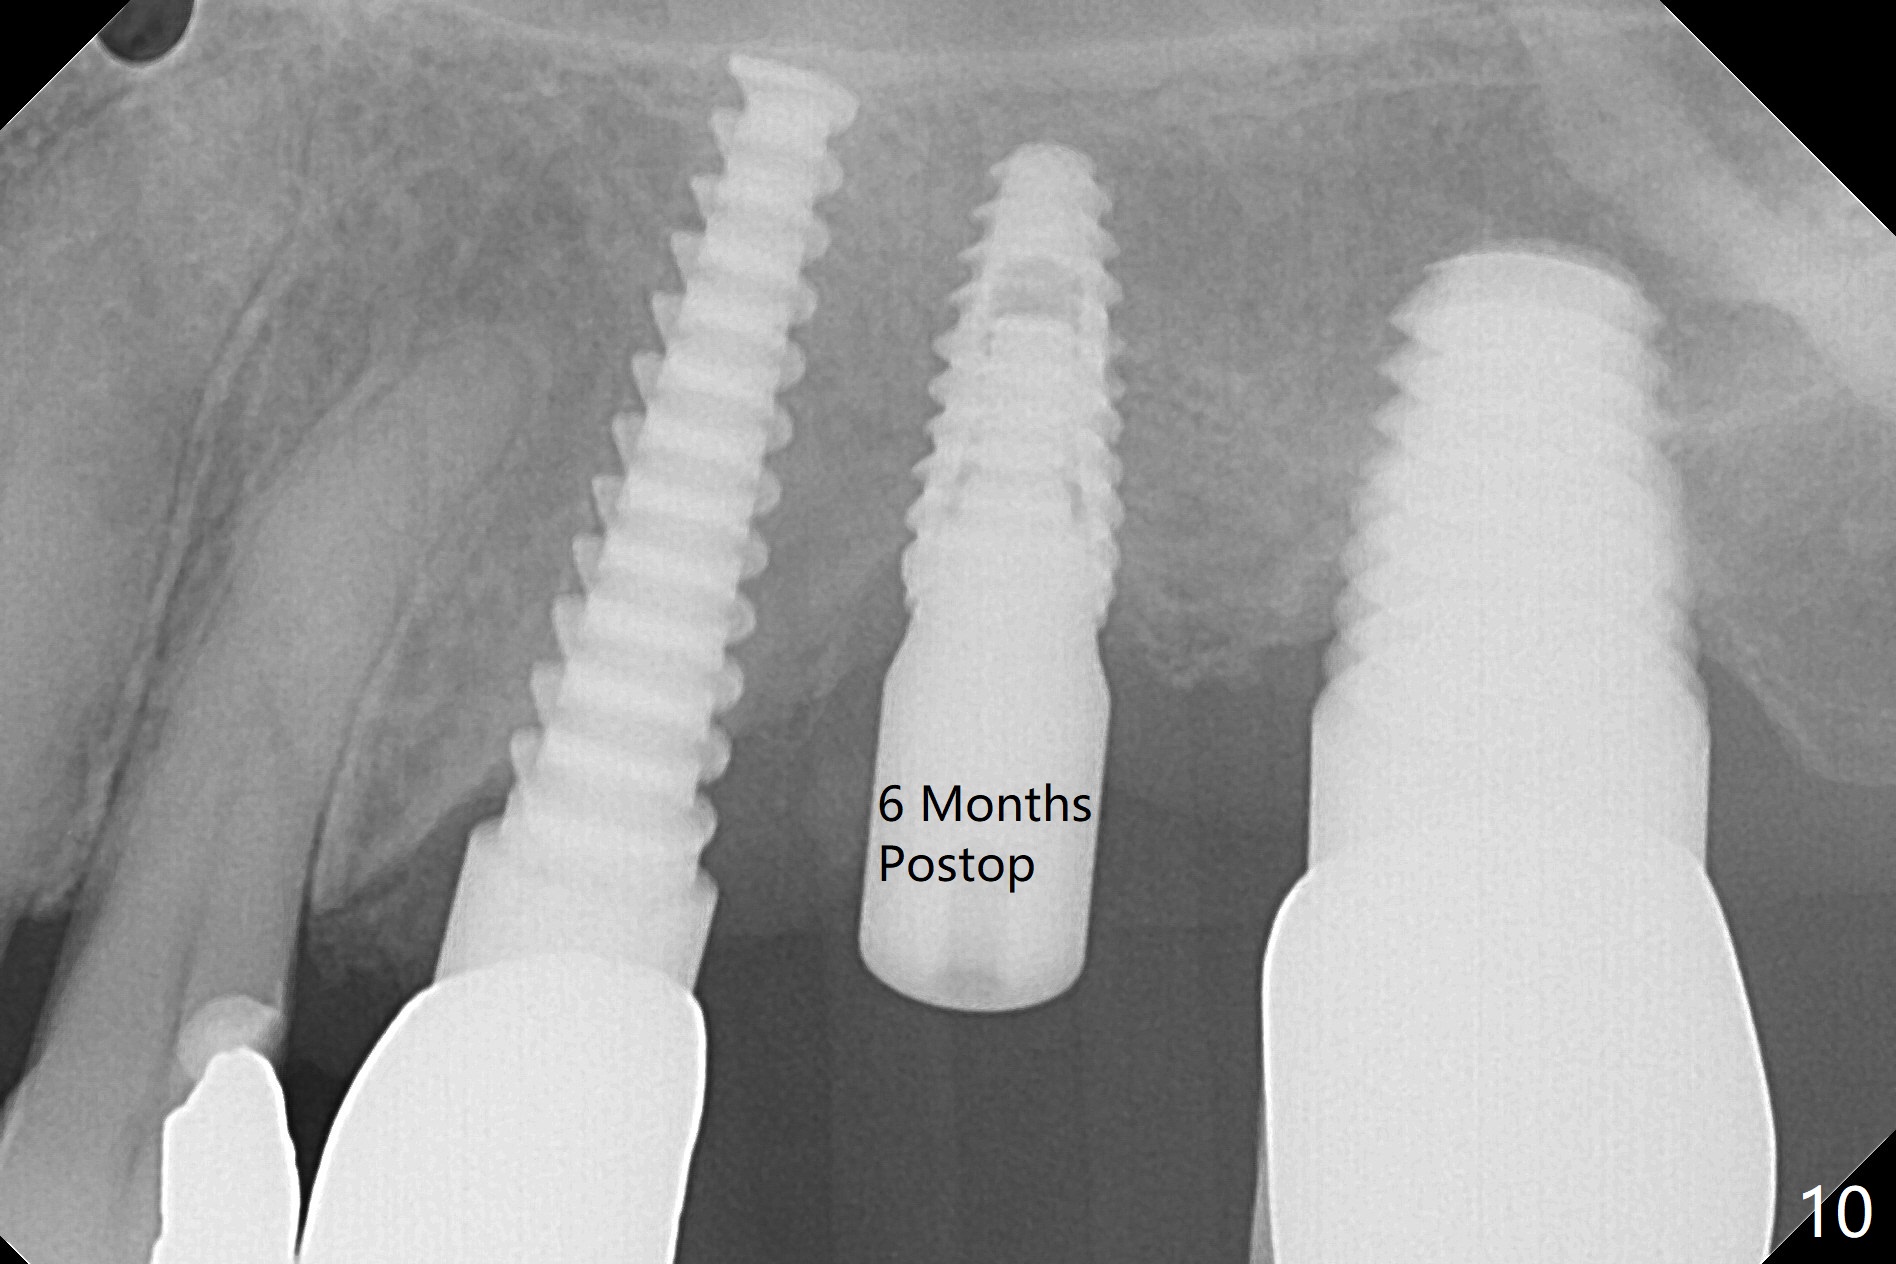

After osteotomy with guide and 2.2 mm drill for ~ 4 mm at #14, a bone expander (1.3/2.3 mm) is used free hand for sinus lift for 12 mm (from the gingival margin, Fig.1; a 10 mm long implant is planned). Following the next expander (1.7/3.1 mm) for the same depth with binding, the sinus membrane is suspected to have perforated. A piece of Osteogen Plug is inserted into the osteotomy as deep as possible with the purpose to repair the sinus membrane (no bone graft being used), followed by placing a 3.5x8.5 (instead of 10) mm implant with insertion torque ~ 25 Ncm (Fig.2,7-9, CT). As compared to preop CT (Fig.4-6), the previously grafted bone is lifted into the sinus by the bone expanders and the implant (Fig.7*). At the same time, the grafted bone has been condensed and pushed buccally (B) (Fig.8,9 *). A 4x6 mm healing abutment is inserted (Fig.3). There is crestal bone loss 6 months postop (Fig.10). Buccal plate atrophy involves the 3 implants in a row (Fig.11). The crown is loose 1 year 8 m post cementation (Fig.12). After proximal reduction, the crown/abutment rotates and sits down substantially (Fig.13). Since the crown is extremely long, it cannot be seated together with the abutment. The latter is seated with X-ray confirmation before proximal reduction of the crown (Fig.14).